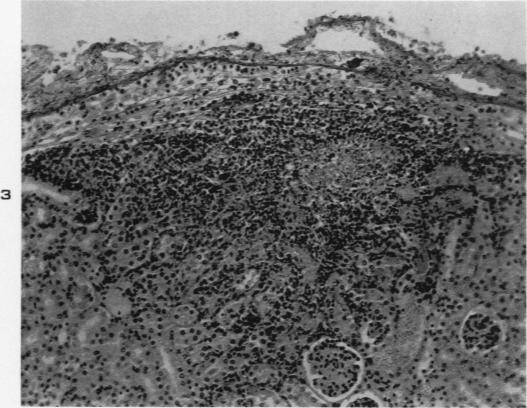

Experimental moniliasis in mice.

Am J Pathol. 1955 Sep-Oct;31(5):859-73.